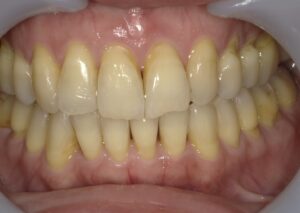

「前歯が大きく重なり、他院で4本抜歯が必要と言われた」という30代女性のケースです。

- 治療方法: インビザライン・コンプリヘンシブ上下

- 治療期間: 1年6ヶ月

- 治療費用: 99万円(税込)

- 治療のリスク・デメリット 装着時間を守らないと期間が延長することがある

- ポイント: 抜歯をせずにIPRと遠心移動を組み合わせ、理想的なアーチを実現しました。